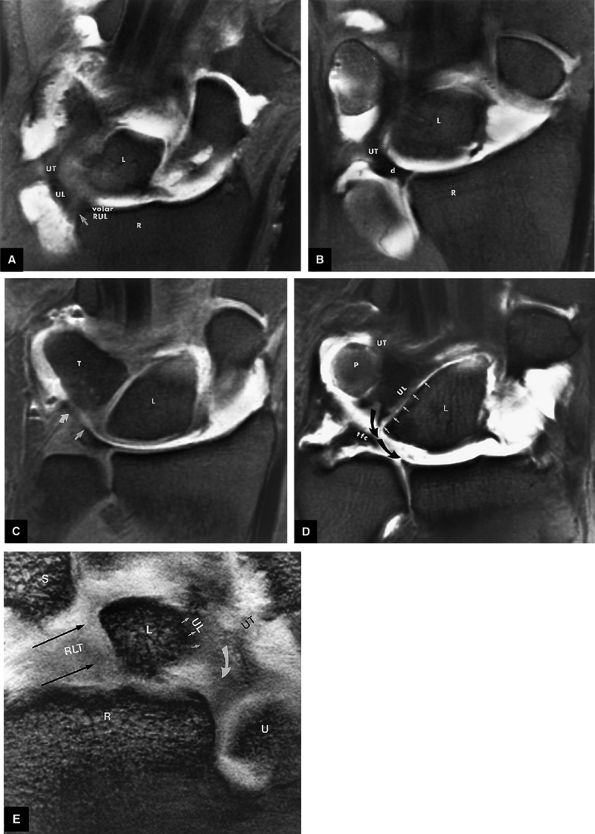

|

FIGURE 10.62 ● Anatomy of the radioscaphocapitate (RSC), radiolunotriquetral (RLT), and radioscapholunate (rsl) ligaments at the level of the distal volar radius (R). T, triquetrum; S, scaphoid. FS T1-weighted arthrogram after radiocarpal injection.

FIGURE 10.63 ● The long radiolunate or radiolunotriquetral (RLT) ligament. (A) The RLT ligament is divided into a radiolunate ligament and lunotriquetral component. The RLT ligament functions as a volar sling for the lunate. L, lunate; R, radius. Volar FS coronal T1-weighted arthrogram. FS axial T1-weighted arthrograms obtained at the level of the proximal (B) and distal (C) aspects of the radial styloid show the volar course of the RLT ligament (large arrows) from the radial styloid (R) inserting into the lunate (L) and blending with the volar portion of the lunotriquetral interosseus ligament. The lunate attachment of the scapholunate interosseous ligament volar fibers is deep to the lunate attachment of the RLT ligament (B). S, scaphoid; T, triquetrum; SL, scapholunate ligament.